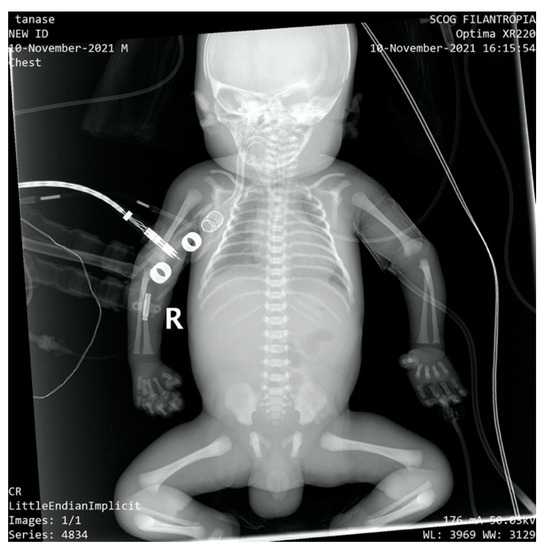

The newborn was admitted to the NICU with an extremely severe condition, pale skin, generalized edema with the appearance of hydrops, generalized purpura, ecchymosis of the cephalic extremity, parietooccipital cephalohematoma, abdomen with important wall edema and ascites fluid. Thoracoabdominal radiography and abdominal ultrasound showed the presence of ascites fluid and poor aeration of the colic frame (Figure 2).

Figure 2.

Thoraco-abdominal X-ray-poor aeration of the colic frame, ascites fluid.

The newborn exhibited hepatomegaly with the right lobe extending caudally. Enlarged hepatic vein and associated splenomegaly were observed on abdominal ultrasound. A cardiac ultrasound revealed mild pulmonary hypertension, mild sized patent ductus arteriosus with left to right shunt, patent foramen ovale with left to right shunt, representing mild cardiac involvement which responded accordingly to the inotrope and vasopressors agents.